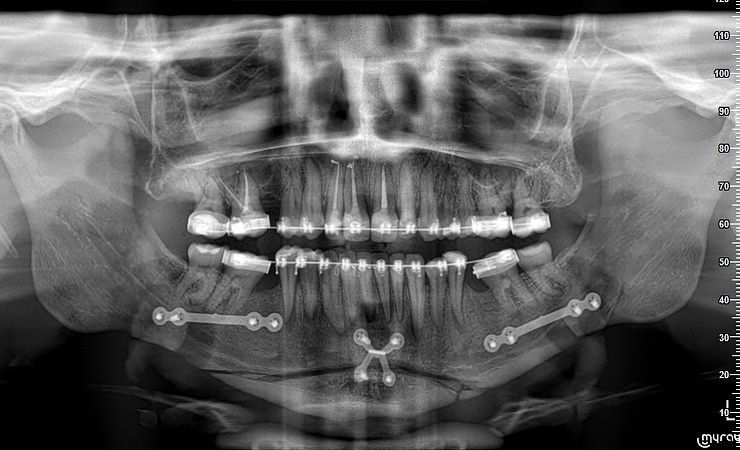

QUEIXO RETRAÍDO

MÁ OCLUSÃO

O tratamento adotado foi uma cirurgia de avanço da mandíbula e mentoplastia.